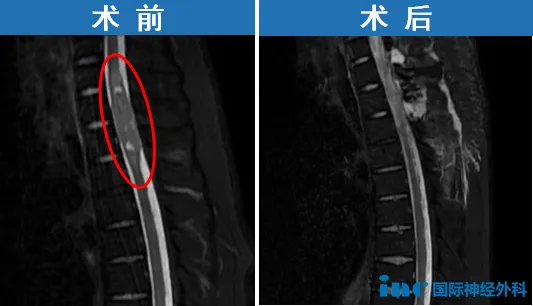

在文昊身上,有3到4个显着的肿瘤需要手术。分别是:胸1至胸3水平的嵴髓内肿瘤,整个腰段椎管内的肿瘤,右侧桥小脑角区肿瘤(一个听神经鞘瘤)以及右侧大脑镰旁的巨大脑膜瘤。

那么应优先处理哪一个?由于文昊患者目前存在剧烈的胸部及上背部疼痛;这与嵴髓内的胸段肿瘤有关。因此,应首先通过显微外科手术处理该病灶。随后可将两个脑部肿瘤(右侧CPA区的听神经鞘瘤及右侧大脑镰旁脑膜瘤)作为下一步的手术目标。

2025年8月15日,苏州大学附属第四医院,文昊顺利手术。手术室外,“谢谢,谢谢!”对于巴教授的万千感谢化作这一句。当巴教授离开时,文昊母亲强忍的泪水终于夺眶而出。“太难了,可是还是坚持下来了!”从孩子患病,到如今,这一条不容易的路他们已经走了26年——这一路的奔波只为让文昊更好的活着。